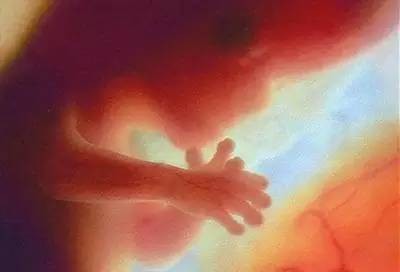

第三个月

胎宝宝和上个月相比,生长迅速,器官也开始工作。头占整个身体的近一半。生殖器发育已经可初步辦认出性别了。通过B超可以观察到胎宝宝四肢活动,肾脏、输尿管形成,可以排泄了。